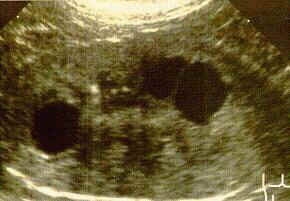

PKD ist das Ergebnis eines "autosomal dominanten" Gens und es ist daher relativ einfach aufzuspüren und auszuschließen. Alle zur Zucht verwendeten Katzen sollten mit Ultraschall untersucht werden um vorhandene Nierenzysten zu erkennen. Es dauert nur einige Minuten mit keiner oder einer kleinen Narkose. Wenn ein positives Ergebnis vorliegt und es möglich ist, dann lassen Sie die Elterntiere testen. Der einfachste Weg diese Krankheit auszuschließen, ist die positiven Tiere zu kastrieren. Wenn ein Zuchttier besonders wertvoll ist, dann ist es möglich PKD-negative Kitten zu bekommen, WENN das eine Elternteil PKD-negativ ist und WENN das positive Elternteil heterozygous ist. (Ist das positive Elternteil homozygous werden NUR positive Jungtiere fallen!!) Wenn die Kitten alt genug sind kann man Sie auf PKD testen lassen. Auf diesem Weg kann man sich seine Blutlinie erhalten und das betreffende positive Elternteil kastrieren. Es ist wahrscheinlich das viel mehr Perser von PKD betroffen sind als zur Zeit diagnostiziert wird. Mit mehr Studien und veröffentlichten Information über diese Krankheit können Züchter und Tierärzte daran arbeiten PKD-freie Zuchtprogramme zu erstellen. Auf diese Weise kann dieses genetische Gesundheitsproblem ausgeschlossen werden.